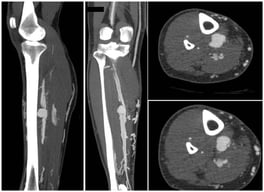

The Middle Meningeal Artery (MMA) occupies a pivotal role in the pathophysiology of migraine, functioning as a vascular and neuroimmune interface that precipitates the characteristic pulsatile pain. The inhibition of this pathophysiological cascade has been investigated as a therapeutic strategy. However, fewer than a dozen centers globally have disseminated procedural or mechanistic data. Given the nascency of this field and the imperative for standardization, the present review synthesizes mechanistic and clinical evidence underpinning intra-arterial pharmacological modulation of the MMA for migraine management. Methods: A focused narrative review was undertaken, drawing upon select but influential studies from pioneering research groups investigating intra-arterial interventions targeting the MMA. The extant literature was thematically categorized and organized according to the loci of cascade interruption and their corresponding clinical outcomes. Results: Since 2009, intra-arterial therapies for severe headache syndromes have evolved, initially utilizing nimodipine for vasospasm-related headaches, progressing to verapamil for reversible cerebral vasoconstriction, and more recently, lidocaine for refractory or status migrainosus, occasionally in conjunction with MMA embolization. Contemporary research uses language that conceptualizes migraine as an immunologically mediated neurovascular disorder, as opposed to a purely vascular or neuronal entity. Recent investigations have identified interleukins such as Interleukin-1β, Tumor Necrosis Factor-α, and Interleukin-6 as critical amplifiers of trigeminovascular activation. Purinergic signaling through the P2X3 receptor and the P2Y13 receptor, in conjunction with pituitary adenylate cyclase-activating polypeptide and vasoactive intestinal peptide pathways, has been implicated in the modulation of MMA excitability and neuropeptide release. The development of novel calcitonin gene-related peptide receptor antagonists, such as zavegepant, further substantiates the artery’s significance as a pharmacological target. Conclusions: These findings support a shift toward immune-modulating intra-arterial therapeutic strategies, with migraine interventions targeting cytokine and neuroimmune signaling within the MMA, rather than relying exclusively on vasodilatory mechanisms.